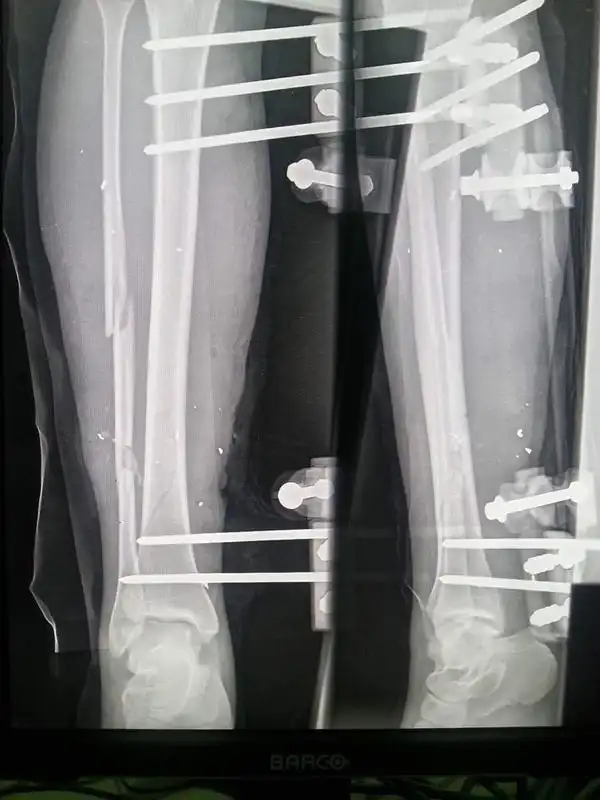

Orthopädische Eingriffe gehören in Krisengebieten zu den häufigsten und dringendsten medizinischen Behandlungen. Bei komplizierten, instabilen Brüchen mit offenen Wunden ist öfters eine Verschraubung mittels Metallrahmen von aussen notwendig. Entsprechend der Funktionsweise werden solche Materialien Fixateur-Externe genannt.

In Nordsyrien ist nach dem Zusammenbruch der medizinischen Versorgung kaum brauchbares Operationsmaterial vorhanden. Importierte Ware aus der Türkei oder China ist zum Teil von sehr schlechter Qualität und den bezahlten Preis nicht wert. Delta konnte mit einem renommierten internationalen Hersteller eine 75% Preisreduktion zur Beschaffung von hochwertigen Fixateur-Externe vereinbaren.

Dr. Ali ist bestens vertraut mit der Anwendung der Fixateur-Externe, er hat hunderte von Erwachsenen und Kindern damit versorgt. Der erfahrene Chirurg ist sowohl für den Transport, als auch für den Einsatz der Materialien vor Ort verantwortlich.